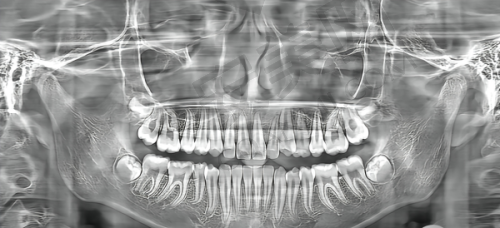

从规模上看,柳州中瑞口腔门诊部占地面积达2200平方米,是柳州地区规模较大的口腔医院之一。医院内部环境优雅、舒适,设有多个独立的诊疗室和手术室,确保了患者的隐私和舒适度。同时,医院还引进了多项精良的口腔诊疗设备和技术,如智能化口腔扫描仪、激光治疗仪等,为患者提供了更加精细、有效的诊疗服务。大规模的场地和精良的设备投入,也从侧面反映出医院的正规性和实力。

柳州中瑞口腔在技术方面表现出色。医院引进了大量国内外精良的医疗设备,如韩国implagraphy三维数字化三合一CT、美国3shape口腔扫描仪、美国itero口内扫描仪等,全部对标北上广机构标准打造。在数字化技术的加持下,中瑞口腔实现了数字化种植、数字化正畸等精良诊疗服务。例如,种植中 心的数字化3D导板定位种植技术,能够精细定位种植体位置,提高手术成功概率;数字化正畸中 心的3D矫正模拟技术,则能提前模拟矫正结果,让患者更加直观地了解治疗过程。